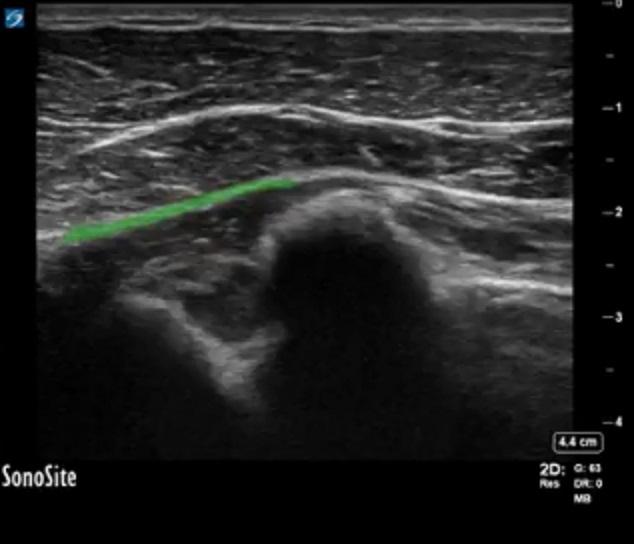

Highlighted Area: Fascia between the serratus anterior muscle and the pectoralis minor muscle (needle target)